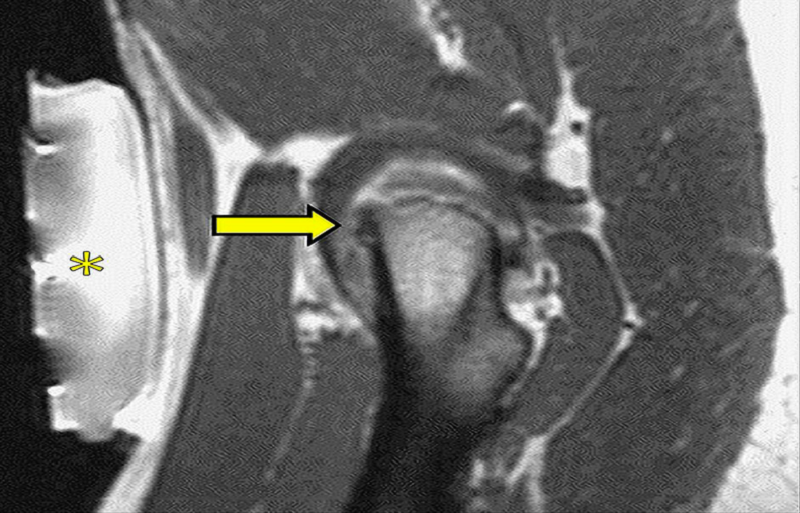

圖:磁共振引導(dǎo)下的復(fù)發(fā)性軟組織腫瘤冷凍消融

活檢和消融是在MRI引導(dǎo)下進(jìn)行的最常見的療法。主要優(yōu)點是無需造影劑即可更好地描繪目標(biāo)。實時多平面成像與高對比度分辨率相結(jié)合,可以準(zhǔn)確定位在非增強(qiáng)CT上定義不清的病灶;此外,在消融過程中,MRI允許監(jiān)測針通路和完全可視化被消融的組織,無論是在基于熱的技術(shù)(由于溫度敏感序列)和在基于冷的技術(shù)的情況下。

另一個優(yōu)點是可以連續(xù)(即使是雙傾角,典型的超聲制導(dǎo)),加上熱控制,評估燒蝕區(qū)域。